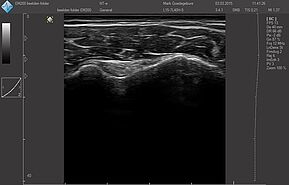

Области исследований:

Система УЗИ поддерживает широкий диапазон трансдюсера нового поколения: монокристаллические, с элементами высокой плотности, широкополОсными и многочастотными от 1,0 МГц до 18,0 МГц:

Датчики имеют большую чувствительность и высокое разрешение, благодаря чему обеспечивают максимальное проникновение и улучшают соотношение сигнал /шум. В результате формируется максимально четкая детализированная картинка УЗИ изображения.

- Усовершенствованная технология уменьшения спекл-шумов